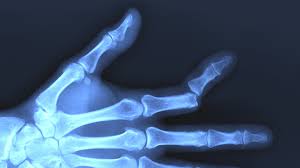

Apply an ice pack to your injured finger and elevate the hand above the level of your heart. Continue elevating your finger when possible. Sometimes, relocating a finger dislocation can be simple and other times it can be very difficult. When a joint is dislocated, the normal alignment of the finger is altered, and the joint must be put back into place. In these challenging situations, there may be tendons or other tissues preventing the joint from going back into position.

There is a broad spectrum of severity of finger ligament injuries, and therefore having these evaluated by your doctor can help ensure that you are not avoiding necessary treatment. A dislocated finger won't move because. In some cases, the damage to the supporting ligaments is significant enough that the joint comes apart, causing an injury called a dislocation. See full list on verywellhealth.com Ice the finger for 20 minutes every few hours for a few days, if you are able.

Thumb sprains and certain finger sprains in children may require a longer period of immobilization or evaluation by a specialist, especially if there is concern that a ligament was torn. To prevent further injury to the finger, immediately remove any. Treatment of a dislocated finger is similar to that of a sprained finger. A dislocated finger won't move because. Remove any jewelry from your dislocated finger. What will happen to my dislocated finger? In this video we demonstrate a metacarpal block and the reduction of a dislocated fifth finger. That said, most finger dislocations can be treated with a simple splint. What is the recovery time for a dislocated finger? You should discuss with your doctor when to begin finger movements. Great exercises that help.in this video i am going to go over so. See full list on verywellhealth.com A finger dislocation is a more severe injury to the digit, as it involves not only the ligament, but also the surrounding joint capsule, cartilage, and other tissues.

How do i treat a dislocated finger? Usually, you'll be able to use your hand as normal within a week, but don't worry if a sprain causes pain and discomfort for a longer period of timethat's normal. Although a dislocation is a more serious injury, expect treatment similar to that of a sprain. When a sprain occurs, a ligament that supports a joint is stretched too far and the tough fibers of the ligament tissue become either partially or completely torn. Other treatments for a sprained finger include: There is a broad spectrum of severity of finger ligament injuries, and therefore having these evaluated by your doctor can help ensure that you are not avoiding necessary treatment. In some cases, the damage to the supporting ligaments is significant enough that the joint comes apart, causing an injury called a dislocation. Other times, the dislocation may require anesthesia or even a surgical procedure to realign the digit. Finger dislocation treatment if you have a dislocated finger, the finger will swell. Once the joint has been put back into position, the finger is splinted to allow the ligaments and joint capsule to heal. In addition to a splint, or sometimes instead of a splint, your doctor may use medical tape to bind your injured finger to an uninjured one next to it. Continue elevating your finger when possible. Remove any jewelry from your dislocated finger.